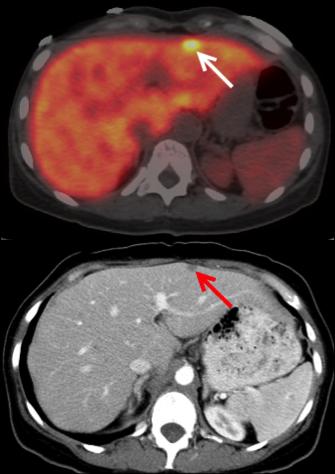

Positron Emission Tomography Scan Pancreatic Cancer Action Network

Positron Emission Tomography Scan Pancreatic Cancer Action Network from www.pancan.org

If a pancreatic mass is seen, that raises the suspicion of. Computed tomography (ct or cat) scan. Jun 01, 2021 · pancreatic ductal carcinoma (pdac) is a highly lethal cancer, and early detection and accurate staging are critical to prolonging survival. Oct 21, 2019 · if pancreatic cancer is present, the likelihood of an ultrasound revealing an abnormality in the pancreas is about 75%. The disease occurs when cells in the pancreas grow, divide, and spread uncontrollably, forming a malignant tumor. Fap is a new target molecule for pet imaging of various tumors. Pancreatic cancer is usually staged following a ct scan. Computed tomography or computerized axial tomography (ct or cat) positron emission tomography ‐ There are three types of ct scan for pancreatic cancer detection. Over 53,000 people in the u.s. The following imaging tests may be used to find out if the bladder cancer has spread and to help with staging. A number of types of pancreatic cancer are known. In this retrospective study, we describe the clinical impact of.

Fap is a new target molecule for pet imaging of various tumors. There are three types of ct scan for pancreatic cancer detection. The disease occurs when cells in the pancreas grow, divide, and spread uncontrollably, forming a malignant tumor. The most common, pancreatic adenocarcinoma, accounts for about 90% of cases, and the term pancreatic cancer is sometimes used to refe. Oct 21, 2019 · if pancreatic cancer is present, the likelihood of an ultrasound revealing an abnormality in the pancreas is about 75%. If a pancreatic mass is seen, that raises the suspicion of. Jun 01, 2021 · pancreatic ductal carcinoma (pdac) is a highly lethal cancer, and early detection and accurate staging are critical to prolonging survival. Pain can be a major problem for people with pancreatic cancer.